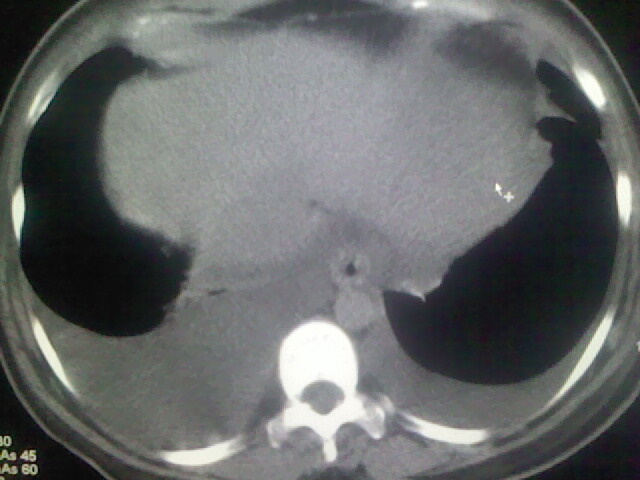

女,24,剖腹产后,突觉胸痛,干咳,不能平卧

肝脾大,双侧胸腔积液,双肺水肿,肺动脉[包括远端小动脉],左右心房,左心室增宽,右心室主动脉无明显改变,符合左心功能不全征;;建议除外二尖瓣关闭不全,扩张性心肌病

肺水肿,双侧胸腔积液,心影增大.考虑妊娠心脏病

考虑产后心肌病,心功能不全,肺水肿,双侧胸腔积液。

风心、心衰。两肺水肿、感染灶及胸水是心衰表现